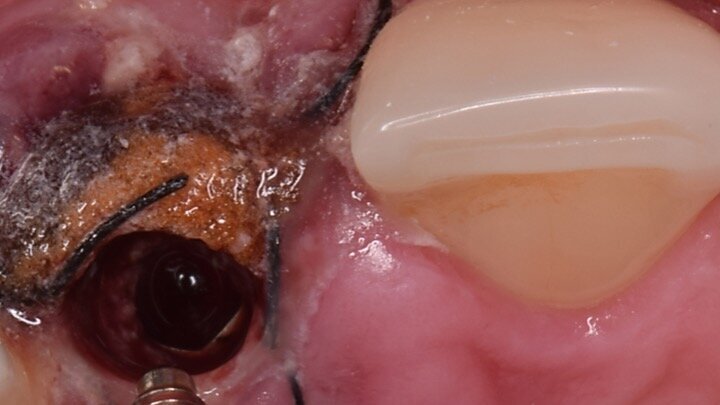

Figura 14. Durante las 24 h. siguientes a la intervención, el paciente tiene que evitar los enjuagues hasta que la prótesis provisional haya sido insertada. Al retirar el pilar de cicatrización temporal podemos observar por fuera la forma que adoptan las membranas de colágeno para cerrar el defecto, y, por dentro, la posición esférica de las partículas debido a su contacto con el pilar.

Figura 15. Observamos el aumento de volumen obtenido por vestibular ante un defecto muy grande. Además, en la emergencia del implante se pueden apreciar las partículas inmersas en la fibrina que posteriormente formarán el nuevo tejido conectivo con el biomaterial en su interior.